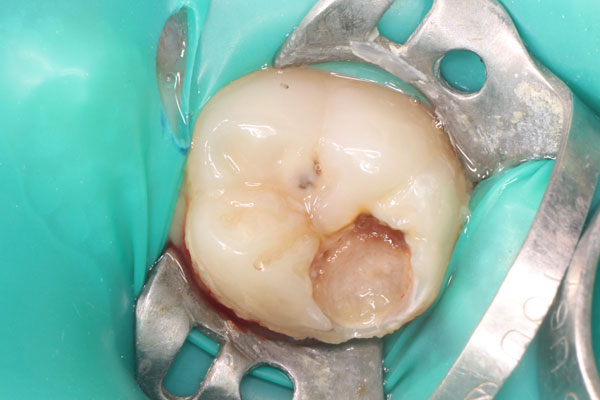

- 2020 - Прямые реставрации жевательной группы зубов (Роман Карпенко)

Если пациентам требуется помощь в области стоматологии, то Юлия Владимировна обладает современными методиками лечения и реставрации зубов, включая зубосохраняющие технологии и профилактику развития стоматологических заболеваний. Её способность проводить лечение зубов под наркозом и седацией обеспечивает комфорт и безопасность для пациентов. Кроме того, возможность проведения манипуляций с применением микроскопа позволяет достичь высокой точности в работе.